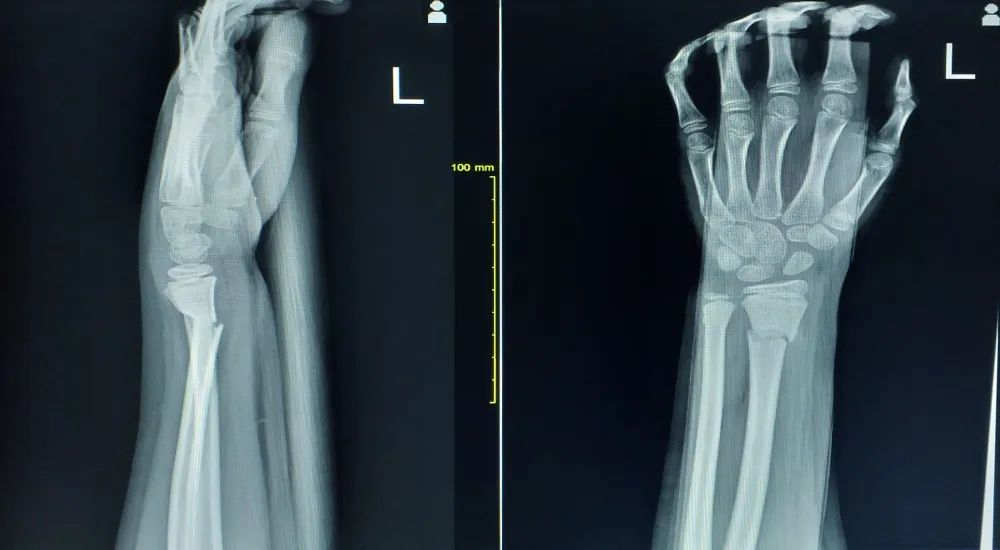

腕银叉状畸形是指桡骨骨折远端连同手部向背侧移位,其近侧有凹陷。这是柯氏骨的典型体征之一。见图1~图2。

图A:解剖图示银叉样畸形;图B:银叉

银叉样畸形X线图像

X线片正侧位示柯氏骨折

典型畸形姿态即侧面看呈「 银叉 」畸形,正面看呈「 枪刺样 」畸形。X 线可见骨折远端向桡、背侧移位,近端向掌侧移位。